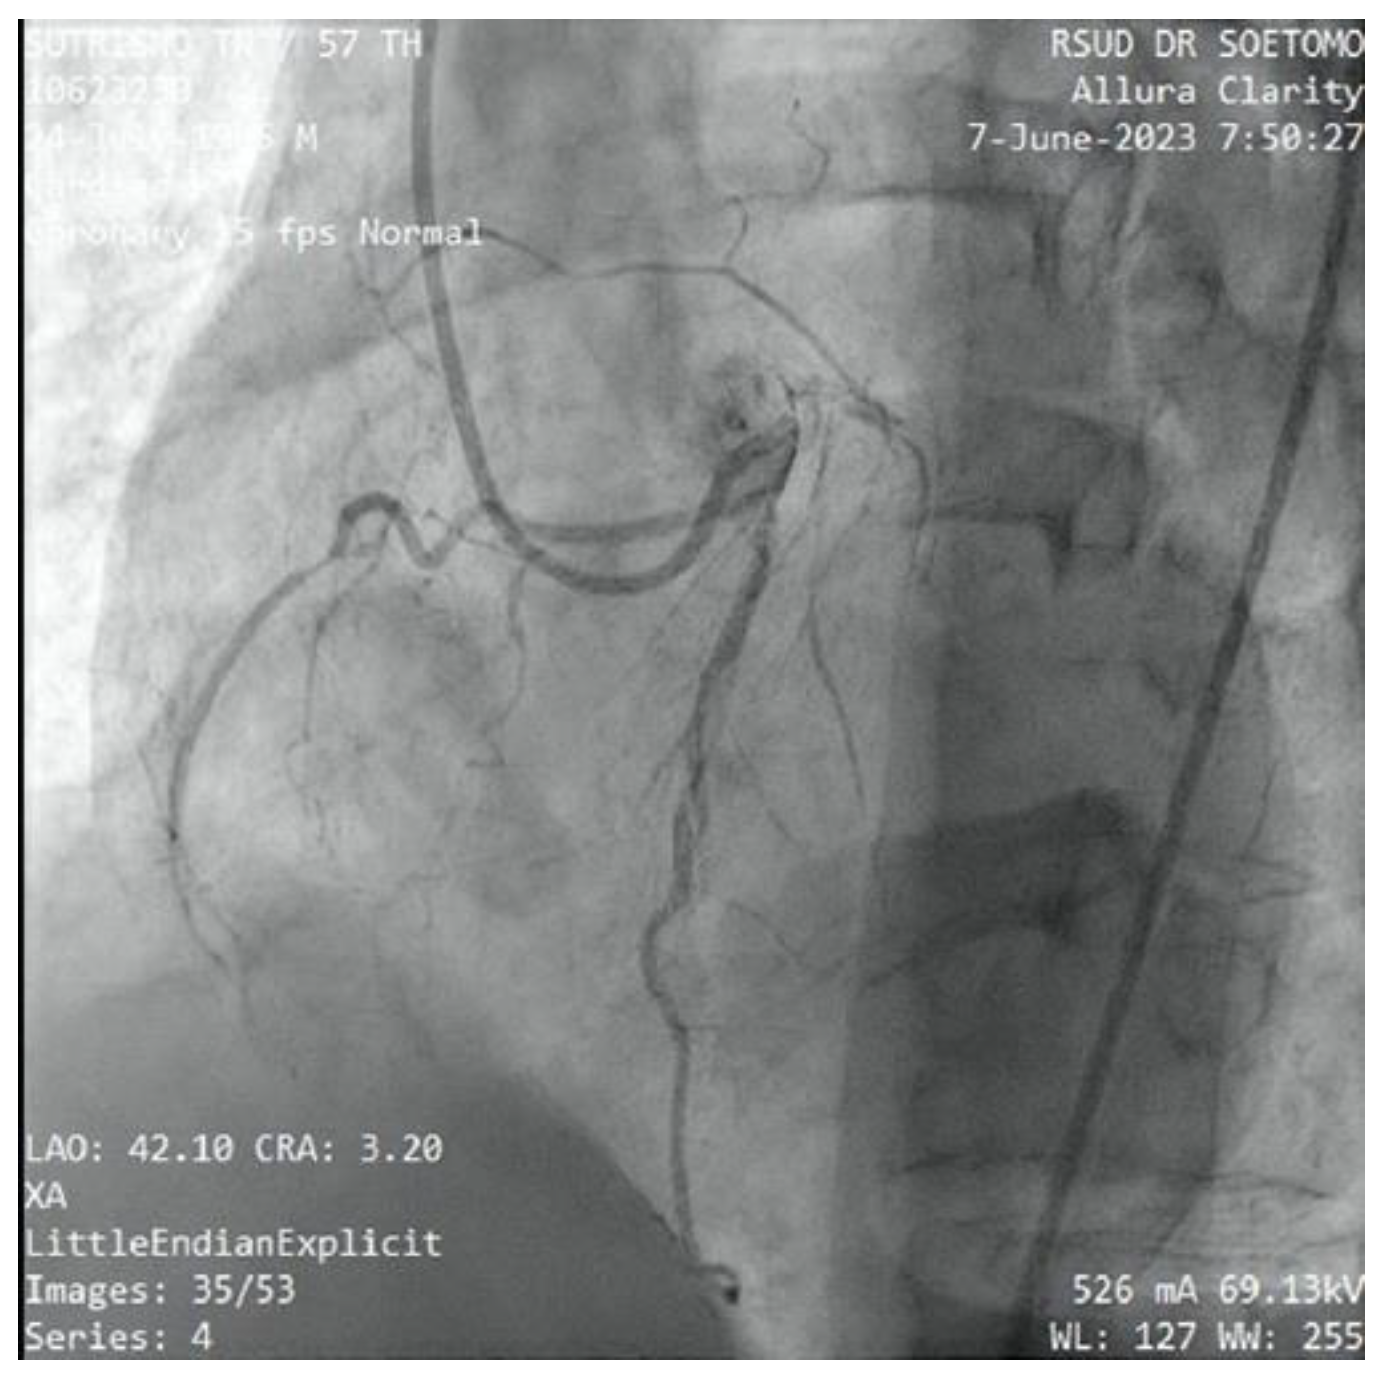

Figure 12. Case #3: The RCA originates from the diagonal branches (D1) in which 90% of the proximal RCA was occluded. .

A 57-year-old male with a history of being a smoker was admitted to our emergency department due to chest pain for 11-hours. He described the pain as 8 of 10 in severity. He also reported associated sweating, blurred vision and the syncope sensation. His family history was unremarkable. His vital signs were as follows: blood pressure 85/61 mmHg and heart rate 45 beats/min. Sulfa atropine 1 vial and dopamine pump 5 gamma was administered due to hypotension and bradycardia. Initial workup revealed hyperlipidaemia and high sensitivity troponin I. ECG showed sinus rhythm, TAVB and upsloping ST depression and peak T wave in V2-V5 leads (de Winter sign) which refers to anterior STEMI (Figure 9). He received a loading dose of aspirin 300 mg and clopidogrel 300 mg for STEMI. We decided to perform percutaneous coronary intervention (PCI). Coronary angiography found triple-vessel disease (TVD) coronary artery disease (CAD), which occluded at the LAD, LCx and RCA, and there was anomalous evidence that the RCA originates from diagonal branches of the LAD (Figure 12).

Following coronary angiography, we discussed the revascularization strategy. PCI was performed the LCX was stent, LAD and RCA occlusion was treated with balloons. During the action, the patient developed hypotension and bradycardia after the balloon implantation to proximal RCA occlusion. Epinephrine 400 nano/kgBW/minutes, vasopressin 300 nano/kgBW/minutes and dopamine 15 mcg/kgBW/minutes was given due to poor hemodynamic status, the patient intubated immediately. Suddenly, the ECG monitor showed asystole rhythm. He got cardiac-pulmonary resuscitation by the team for 30 minutes and was given epinephrine 1 mg for 8 times. Unfortunately, the patient did not survive from the cardiac arrest.